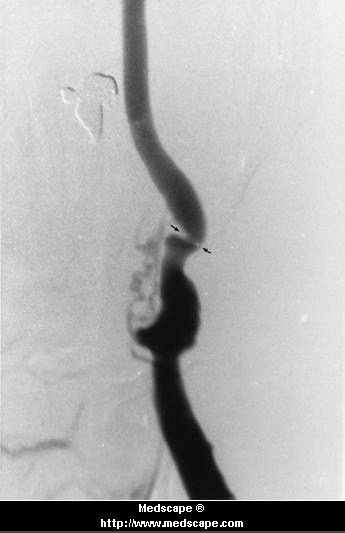

carotid stenosis before (arrows) and after PTCA/stent